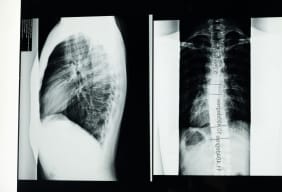

Find out about the scoliosis x-ray process and how to tell if you have scoliosis, as well as MRI for scoliosis.